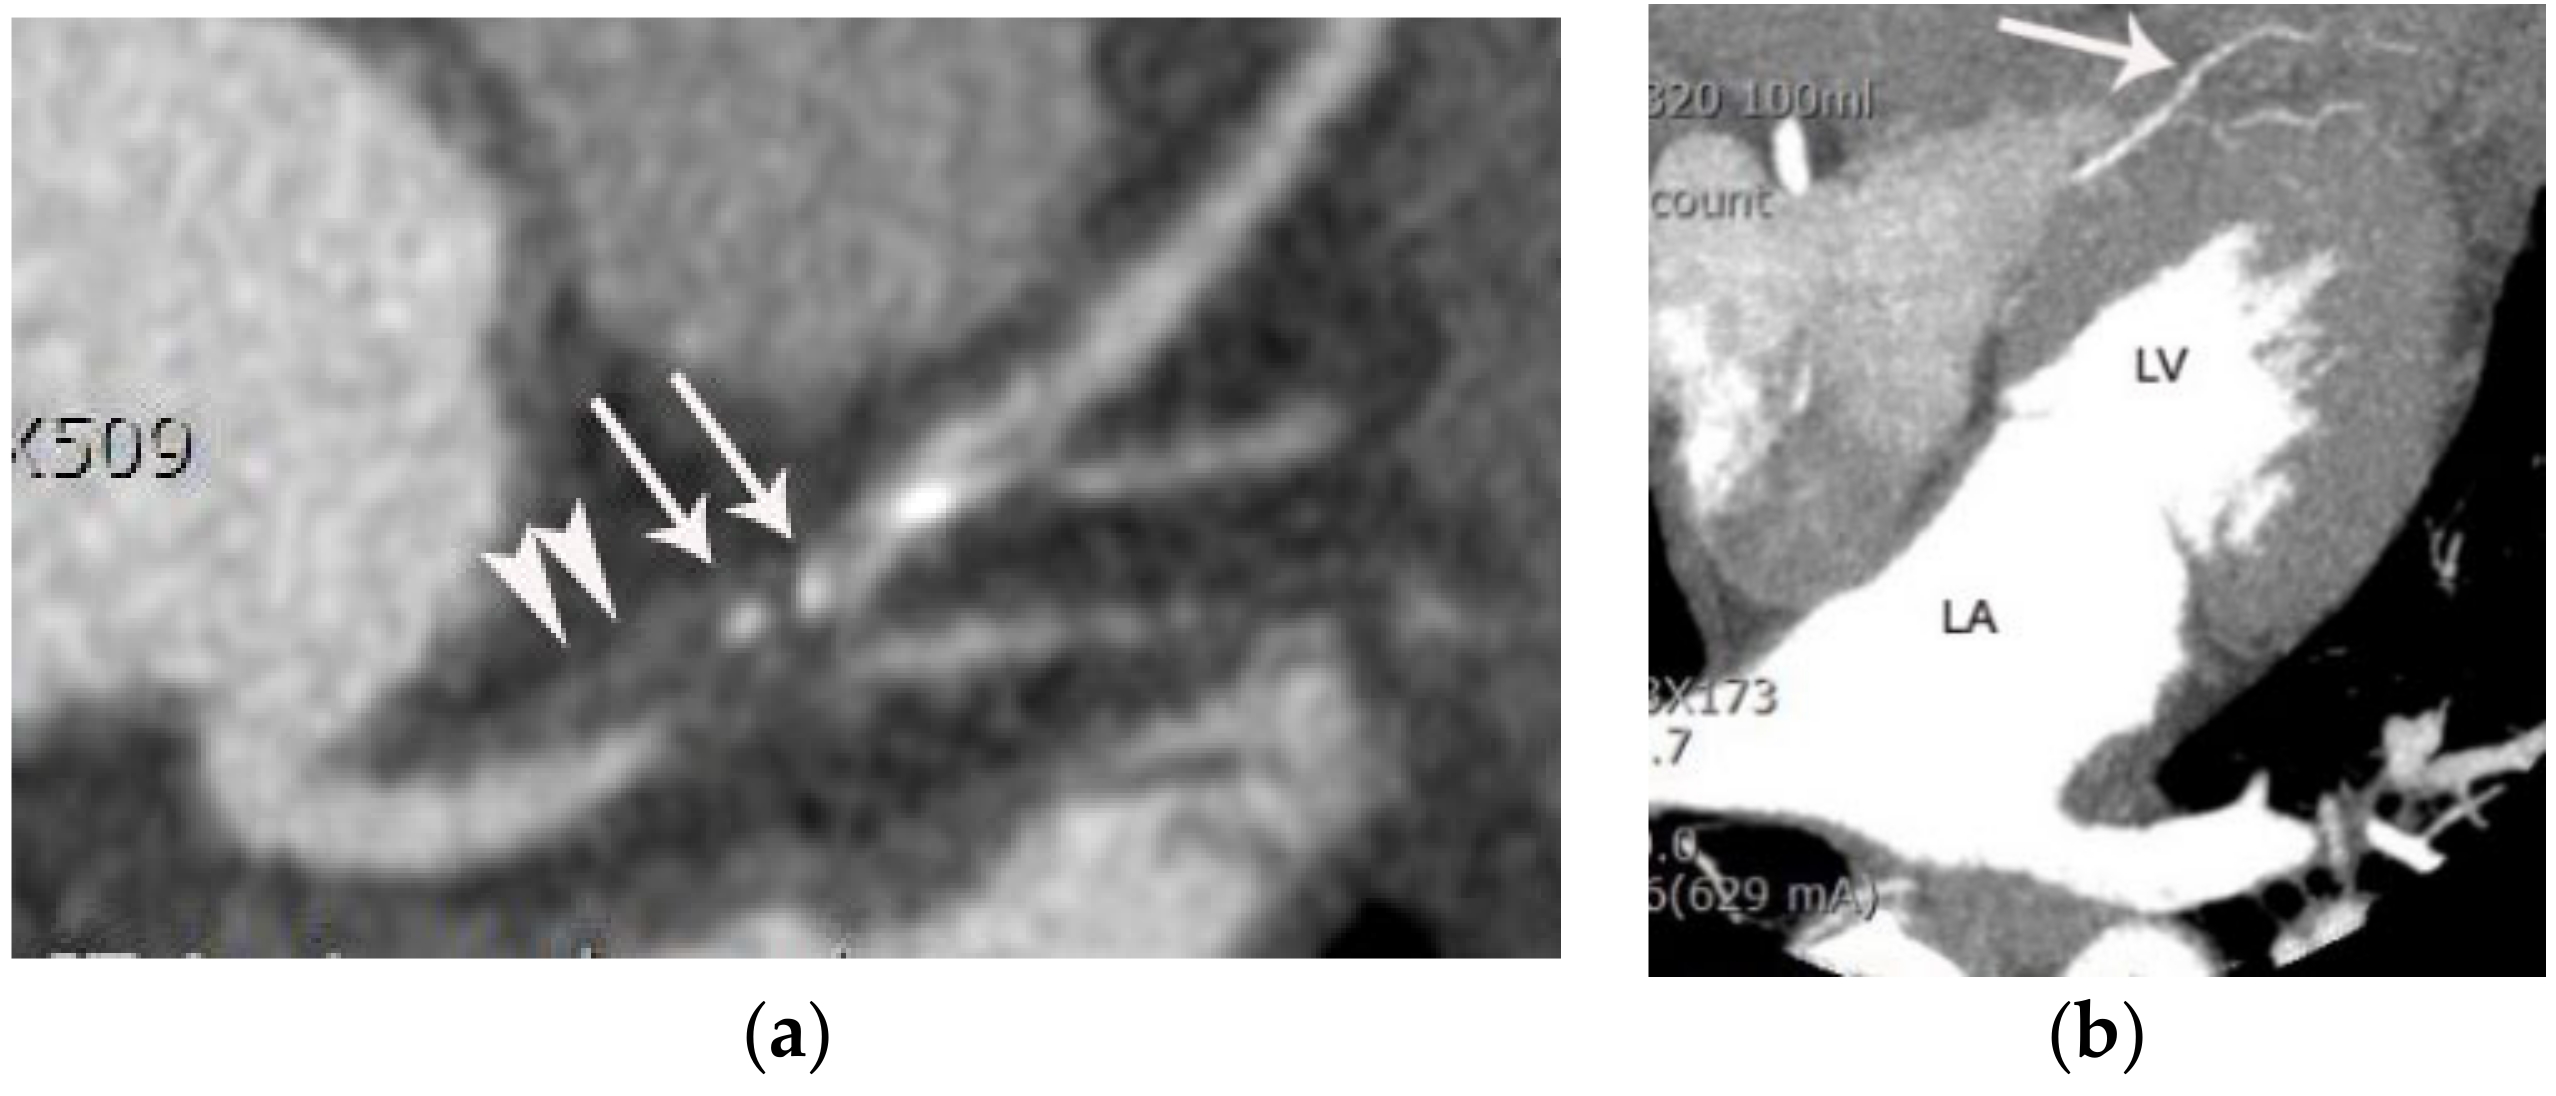

Culprit Plaque of Type 1 Acute Myocardial Infarction

4.3. Epicardial Fat Abnormality of Acute Coronary Syndrome

- Motoyama, S.; Kondo, T.; Sarai, M.; Sugiura, A.; Harigaya, H.; Sato, T.; Inoue, K.; Okumura, M.; Ishii, J.; Anno, H.; et al. Multislice computed tomographic characteristics of coronary lesions in acute coronary syndromes. J. Am. Coll. Cardiol. 2007, 50, 319–326. [Google Scholar] [CrossRef]

- Chun, E.J.; Han, J.H.; Yoo, S.M.; Lee, H.Y.; Song, I.S.; White, C.S. Differences in the CT findings between vulnerable plaque and culprit lesions in acute coronary syndrome. J. Cardiovasc. Comput. Tomogr. 2018, 12, 115–117. [Google Scholar] [CrossRef]

- Maurovich-Horvat, P.; Hoffmann, U.; Vorpahl, M.; Nakano, M.; Virmani, R.; Alkadhi, H. The napkin-ring sign: CT signature of high-risk coronary plaques? JACC Cardiovasc. Imaging 2010, 3, 440–444. [Google Scholar] [CrossRef] [PubMed]

- Hedgire, S.; Baliyan, V.; Zucker, E.J.; Bittner, D.O.; Staziaki, P.V.; Ap Takx, R.; Scholtz, J.-E.; Meyersohn, N.; Hoffmann, U.; Ghoshhajra, B. Perivascular Epicardial Fat Stranding at Coronary CT Angiography: A Marker of Acute Plaque Rupture and Spontaneous Coronary Artery Dissection. Radiology 2018, 287, 808–815. [Google Scholar] [CrossRef] [PubMed]